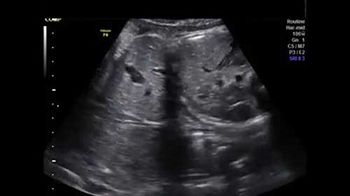

Challenge your diagnostic skills: Is everything normal in this fetal abdomen?